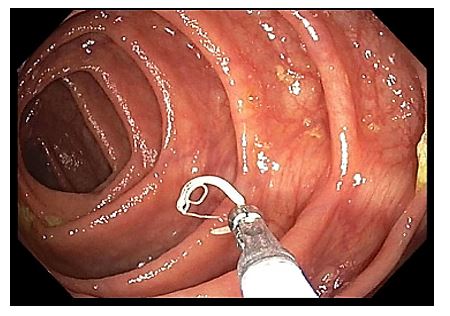

A 26 year old male presented to the emergency department (ED) with 1 week of malaise, high nightly fevers, abdominal pain, dark urine, and dysuria. He had no past medical history and was not taking any medications. He had been living in shelters since arriving in the US approximately 1 month ago after several months traveling through South and Central America from Venezuela. On review of systems, he also reported 3-4 days of constipation and a single episode of non-bilious, non-bloody vomit 2 days ago, accompanied by nausea. He denied mosquito bites, bloody or dark stools. On physical exam, patient appeared thin, mildly jaundiced, and had LUQ/LLQ moderate tenderness to palpation without guarding and splenomegaly. Given his travel history and presenting symptoms, the infectious disease service was consulted, and blood was drawn in the ED for further analysis. CBC and CMP were significant for normal WBC (10.21 x 103/mcL), normocytic anemia (hemoglobin 11.3 gm/dL, MCV 80.4 femtoliters), thrombocytopenia (48 x 103/mcL), hyperbilirubinemia (total bilirubin 2.4 mg/dL, indirect bilirubin 1.7 mg/dL), and slightly elevated AST (46 units/L). Thin blood smear showed relatively enlarged erythrocytes infected with multiple ring forms and trophozoites with ameboid cytoplasm, consistent with Plasmodium vivax. Parasitemia was calculated to be 0.4%. The patient was diagnosed with uncomplicated malaria and started on artemether-lumefantrine for 3 days. He was found to a severe deficiency (41 units/1012 RBC) of glucose-6-phosphate dehydrogenase (G6PD) and therefore, at high risk of hemolysis if administered primaquine. Given his complex social situation, the patient decided to monitor himself for symptoms of relapse and defer starting primaquine for treatment of the liver stages of P. vivax. He was discharged to a local shelter with plans to follow-up closely with the outpatient infectious disease department, with strict precautions to return to the ED urgently for recurrent symptoms.

Malaria should be suspected when a patient presents with a febrile illness and a travel history within a malaria-endemic region. Diagnosis of P vivax can be made through microscopic examination of blood smears, immunochromatographic rapid diagnostic tests (RDTs) and nucleic acid detection through amplification techniques.1 Examination of a thick blood smear allows efficient screening for malaria parasites, while a thin blood smear allows for species identification since parasite morphology is more clearly visualized.2 Upon examination of thin blood smears, infections by P. vivax and P. ovale may appear indistinguishable as both species infect immature, enlarged erythrocytes (1.25-2x normal), can be visualized at any stage in peripheral blood (ring, trophozoite, schizont, and gametocyte) and because Schuffner’s dots are a common morphologic feature during most stages. Defining characteristics of P. vivax include the presence of a large, ameboid trophozoite cytoplasm, and fine Schuffner’s dots and schizonts with >12 merozoites. Of note, preparation with Giemsa stain over Wright stain is preferred for demonstration of Schuffner’s dots.2 Immunochromatographic RDTs detect parasite-specific antigens (e.g., Plasmodium lactate dehydrogenase, Plasmodium specific aldolase) in a finger-prick blood sample. These tests are commercially available and relatively simple to perform and interpret, making them a useful tool for resource-limited regions.1 Nucleic acid amplification-based tools (e.g., PCR, loop-mediated isothermal amplification) are not routinely used for clinical management of malaria but do have diagnostic advantages over light microscopy and RDTs.3 PCRs are highly sensitive, can detect mixed infections even at low parasite densities, and are useful for epidemiological studies such as drug resistance identification.1